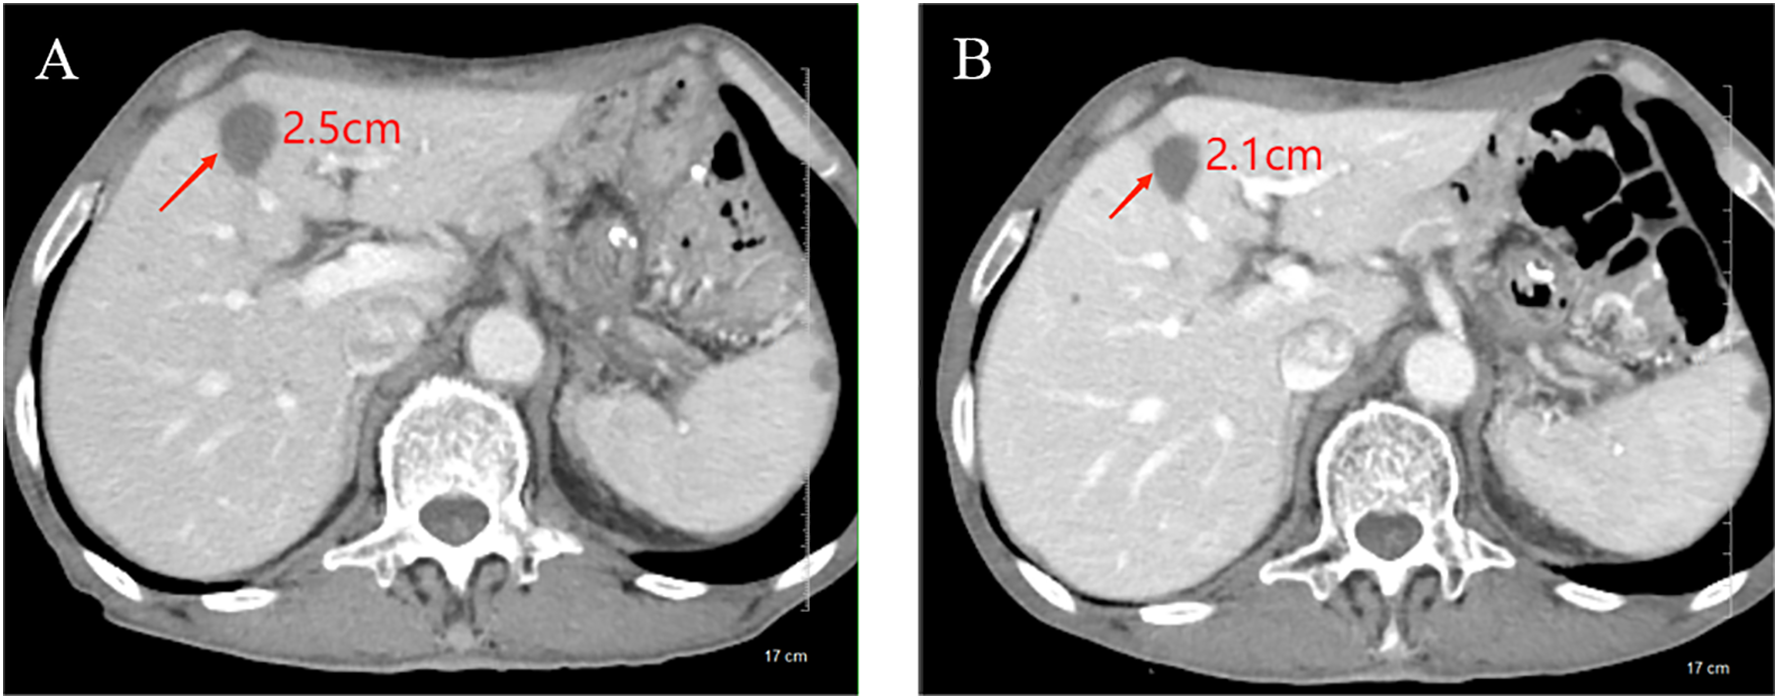

In February 2023, he was admitted to our department with an worsen eating obstruction. Chest and abdominal computed tomography (CT) scan showed cardia recurrence and multiple metastases in liver, peritoneum, abdominal cavity and retroperitoneal lymph nodes. Sintilimab (200mg, intravenously every three weeks) combined with nanoparticle albumin-bound paclitaxel(300mg, intravenously every three weeks) was admitted as first-line treatment after recurrence. After 4 cycles of chemotherapy plus ICI therapy, the patient´s metastases were significant shrink (Figure 1), but the cardia lesions were almost unchanged. As the patient strongly requested further relief of eating obstruction, we implemented exploratory local injection of H101 into recurrent cardia lesion by painless gastroscopy with the patient’s full knowledge and consent. Since June 9, 2023, H101 (5.0×1011 virus particles/0.5ml every time) was multipoint injected by painless gastroscopy every six weeks (8), 1 day before Sintilimab in each cycle. We observed on CT and gastroscopy images that the cardiac lesion were significantly reduced after two H101 treatment (Figure 2). Meanwhile, the patient´s eating obstruction symptom was subsequently relieved. Before and after two H101 treatment, we biopsied the cardia lesions and performed immunohistochemical staining of CD4+T cells and CD8+T cells respectively, results revealed a significant promotion of CD4+ T cell infiltration after H101 treatment (Figure 3). Unfortunately, no significant infiltration of CD8+T cells was found after H101 treatment (Figure 4). Then Sintilimab combined with S-1(60mg orally twice daily for 14 days) was admitted as maintenance antitumor therapy to date. (The timeline of treatments is shown in Table 1).

Figure 1

www.frontiersin.org

Figure 1. Comparison of longest diameter of liver metastases on CT images before and after chemotherapy plus ICI therapy. (A) Before treatment, the longest diameter of liver metastases was about 2.5cm; (B) After treatment, the longest diameter of liver metastases was reduced to 2.1cm.